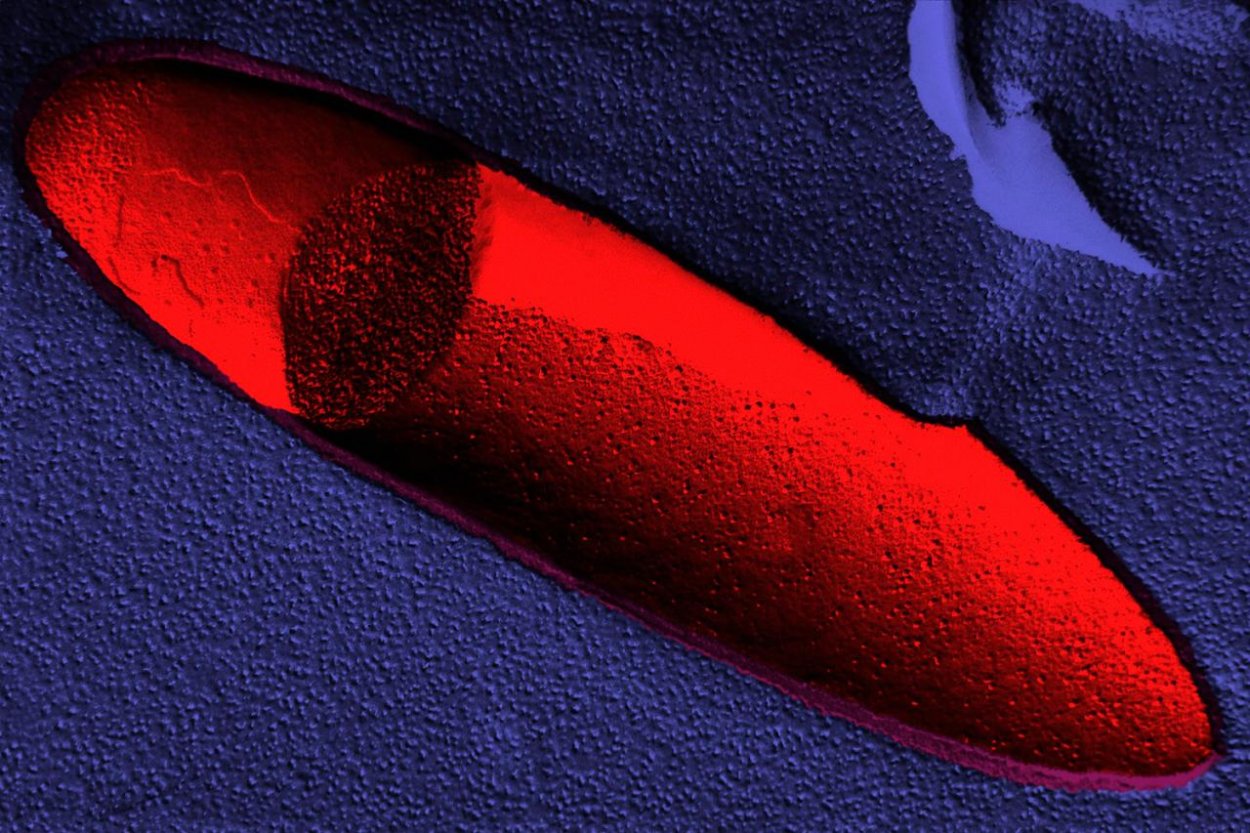

snáď neexistuje niečo, čo by v ľudskom organizme baktérie neovplyvňovali – majú podiel na fungovaní mozgu až po psychickú pohodu. Keďže výskumy dokladujú, že zásadné osídlenie baktériami sa deje už pred narodením dieťaťa, toto poznanie je ďalším vážnym dôkazom toho, aký dôležitý je správny a bezpečný pôrod. A nebude prekvapivé, ak prezradíme záver dopredu – absolútne najlepší je ten prirodzený. A to aj pre správnu bakteriálnu výbavu.

Prednosta Gynekologicko pôrodníckej kliniky v Nemocnici Ružinov v Bratislave Jozef Záhumenský začína zoširoka. Nebolo to tak dávno, čo si lekári pôvodne mysleli, že plod vyrastá v maternici v prísne sterilnom, bezbaktériovom prostredí. „Predtým sme mali len jednoduché vyšetrovacie metódy, ako napríklad kultiváciu, ktorá nezachytila malé množstvo baktérií. Najnovšie genetické metódy však dokazujú, že už v plodovej vode, na placente, aj na samotnom plode sa baktérie nachádzajú aj za normálnych okolností a ovplyvňujú vývoj plodu,” vysvetľuje Záhumenský.

Baktérie nachádzajúce sa na placente majú pritom zaujímavé zloženie. Záhumenský vysvetľuje, že sú totožné s tými, ktoré má tehotná žena v ústnej dutine. Tie prechádzajú krvou až k plodu. Preto je dôležité, aby sa žena, ktorá plánuje otehotnieť, dôkladne starala o zdravú ústnu dutinu. Akýkoľvek zápal v nej dokonca zvyšuje riziko predčasného pôrodu.

„Najmä laktobacily a bifidobaktérie dokážu u novorodenca naštartovať zdravú imunitu.